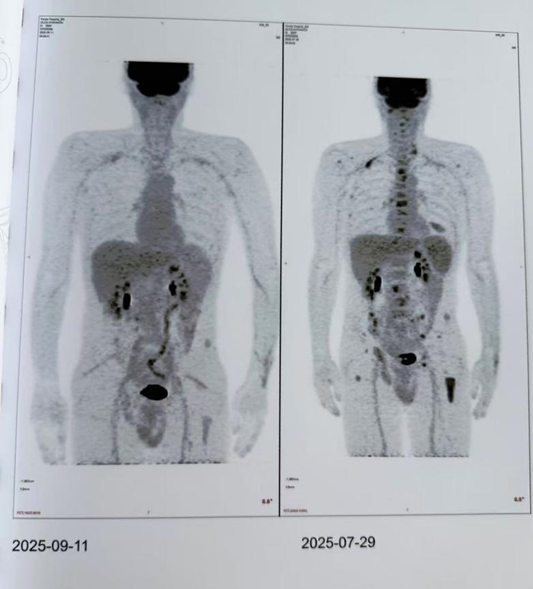

PET/CT:全身多骨多发代谢活性中度增高灶,尤其是左侧股骨上段,左侧第 7 侧肋及右侧耻骨、坐骨,考虑多发性骨髓瘤,部分合并病理性骨折

回输后第 29 天,更令人振奋的消息传来:骨髓微小残留病变(MRD)评估显示「未见恶性细胞」,PET/CT 检查显示,全身骨骼的病灶代谢活性已显著降低,病情得到全面控制,——这意味着疾病达到了完全缓解!